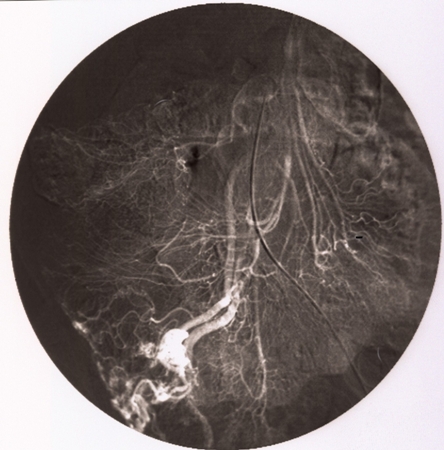

In patients with acutely bleeding lesions (equivalent to 3 units of blood loss per day) and non-diagnostic colonoscopy, CT angiography should be performed to assess the arterial anatomy and localise the bleeding point, followed by mesenteric angiography with a view to embolisation.[39][Figure caption and citation for the preceding image starts]: Ileocolic artery on mesenteric angiogram. Vascular tufts and tangles from local mass of irregular vessels displayedImage donated by Dr DeNunzio, Derby, UK [Citation ends].

[Figure caption and citation for the preceding image starts]: Mesenteric angiogram. Early and intensely filling vein resulting from direct arteriovenous communicationImage donated by Dr DeNunzio, Derby, UK [Citation ends].

[Figure caption and citation for the preceding image starts]: Mesenteric angiogram. Persistent opacification beyond normal venous phaseImage donated by Dr DeNunzio, Derby, UK [Citation ends].